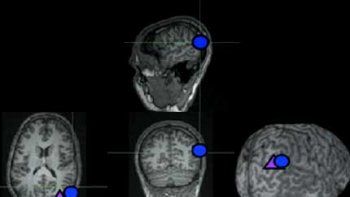

Un implante funciona enviando señales al cerebro. El proyecto cuesta 42 millones de dólares y estará listo en 2013. Australia: Hicieron un ojo biónico